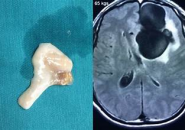

Để kiểm tra amip, các bác sĩ chọc dò tủy sống để lấy mẫu dịch não tủy và đôi khi lấy một mẩu mô não nhỏ (sinh thiết), sau đó kiểm tra và phân tích mẫu thu được.

Các bác sĩ nghi ngờ bệnh viêm màng não do amip nguyên phát ở những người có triệu chứng và mới bơi trong nước ngọt, nhưng chẩn đoán rất khó xác nhận. Các xét nghiệm hình ảnh, chẳng hạn như chụp cắt lớp vi tính (CT) và chụp cộng hưởng từ (MRI), được thực hiện để loại trừ các nguyên nhân có thể khác gây nhiễm trùng não, nhưng chúng không thể xác nhận rằng amip là nguyên nhân.

Chọc dò tủy sống (chọc dò thắt lưng) được thực hiện để lấy mẫu dịch não tủy (chất lỏng bao quanh não và tủy sống). Xét nghiệm này có thể loại trừ một số nguyên nhân khác có thể gây viêm màng não và nhiễm trùng não , nhưng không phải lúc nào các bác sĩ cũng có thể tìm thấy amip trong mẫu xét nghiệm.

Sinh thiết mô não được nhuộm và kiểm tra dưới kính hiển vi hoặc phân tích bằng PCR